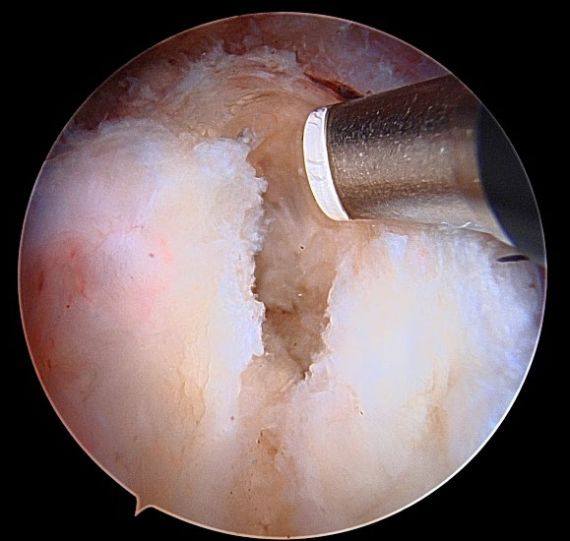

Operative Treatment for Proximal Hamstring Tears

Minimally invasive surgery can be performed either through one small incision in the posterior thigh (as seen below) or through 3-4 poke hole incisions with the use of a camera and special instruments. The tendons are reattached to the posterior pelvis (ischium) with suture anchors.